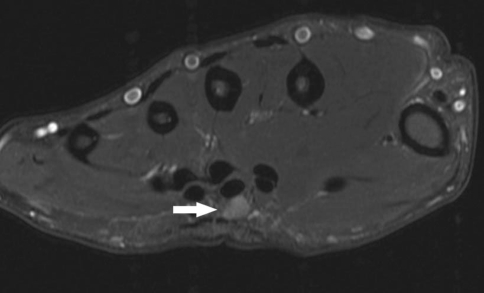

Fig. 2.

The mass (arrow) is hyperintense on T2-weighted MRI and again is deep to the palmar fascia but superficial to the flexor tendons in the palm.

T1-weighted MR images showed a well-defined 5-mm rounded mass lying just deep to the palmar fascia and superficial to the flexor tendons at middiaphyseal level between the index and long metacarpals. The lesion abutted but did not envelope or substantially displace the adjacent flexor tendons. The lesion was isointense to muscle (Fig. 1). Further sequencing revealed the mass to be homogeneous and hyperintense on T2-weighted imaging, suggesting the possibility of a fluid component to the mass. No surrounding edema was noted on the T2-weighted images (Fig. 2). No contrast was administered.